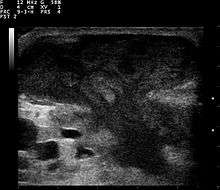

Ultrasound image of breast abscess, appearing as a mushroom-shaped dark (hypoechoic) area

An abscess is a localized collection of pus (purulent inflammatory tissue) caused by suppuration buried in a tissue, an organ, or a confined space, lined by pyogenic membrane.[18]